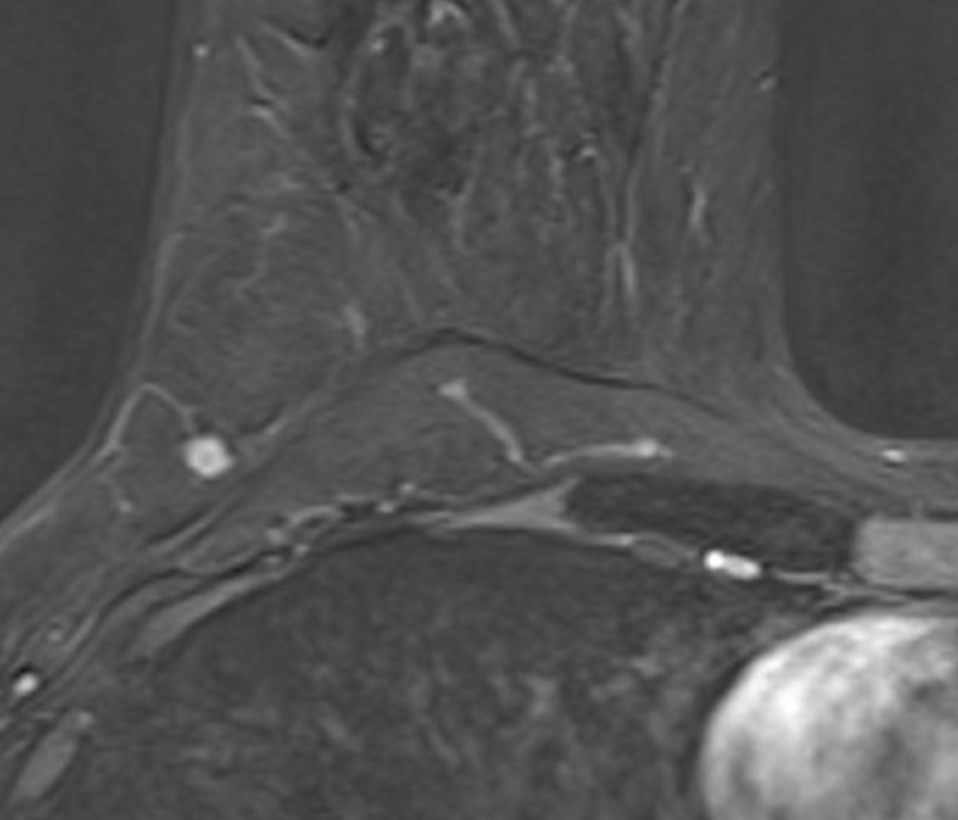

Warum schmerzt die Hand? Ihre Diagnose! Wie klassifizieren Sie die Pathologie?